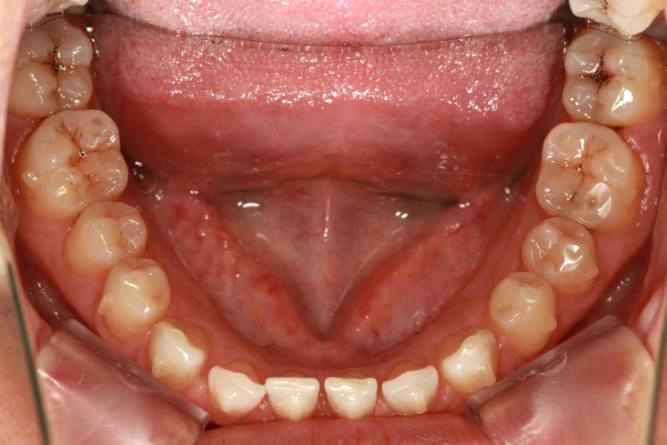

Angle Class III, bony class I Dentition space

Symptoms:Dentition space

1. The upper and lower anterior teeth are scattered in the space.

2. 16 #, 17 #, 26 #, 27 #, 38 #, 37 #, 36 #, 46 #, 47 #, 48 # caries.